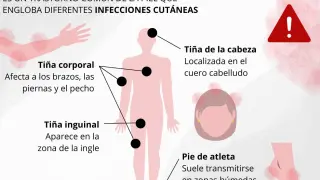

- Erupción cutánea.